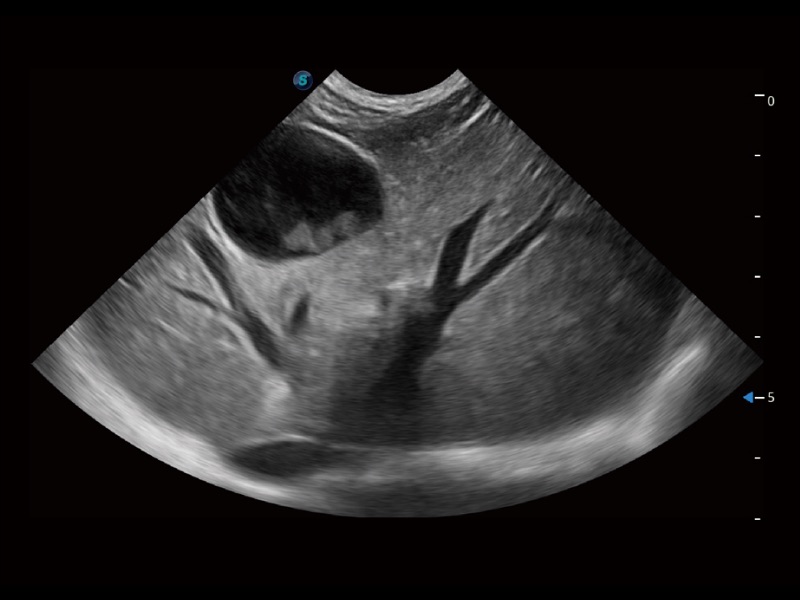

优异的基础图像

ProPet 70 全新的动物超声智能软件和丰富的探头群,为动物医生提供了高清晰度和精细分辨率的图像,无论在宠物、马科、畜牧还是实验室动物等应用中都可以轻松应对,为您的日常工作带来满意的体验。

(犬)肝脏